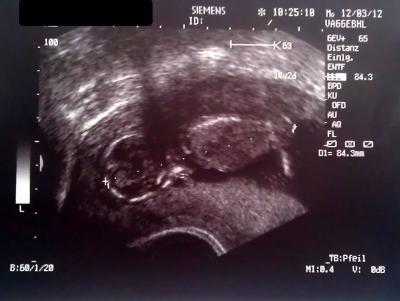

Hier noch mein Bild von heute, habe es nun doch eingescannt. Es ist leider nicht so ganz ran gezoomt wie das letze mal aber das Baby ist 1,5 cm in einer Woche gewachsen. Und es ist auch nicht ganz sooo toll wie das andere, auf dem anderen hat man mehr Details erkannt, trotzdem möchte ich euch das Bild nicht vorenthalten :-D

Das stimmt hauptsache dem Baby gehts gut, der Arzt hat es halt nicht so schön rangezoomet, wie ich es mir gewünscht hätte, es sieht jetzt so aus als wäre das das jüngere Bild und das vorherige halt das ältere. Hier nochmal das vorherige Bild:

Is doch nen schönes Bild. Aber nur mal kurz angemerkt. Wenn du lt. Bild 14+2 bist, dann bist nicht 14.ssw, sondern bereits 15.ssw. lg

Hey, nein nein die zahl auf dem Bild stimmt nicht, nach der größe vom Kind wäre ich so weit, aber da ich genau einen Eisprung mit Temperatur berechnet habe, bin ich heute erst bei 13+3. :-)

Hey :-) Das mit dem Sodbrennen kenne ich, ist wirklich schlimm manchmal. Ich hab momentan eine blöde Blasenentzündung :-( tut ganz doll weh, hab heute Antibiotikum genommen und hoffe das die Schmerzen jetzt bald hoffenltich völlig aufhören. Schön, dass deine Beschwerden nachgelassen haben :-), dann kannst du die Schwangerschaft richtig genisen. Mein Arzt hat mich nicht weiter gestuft weil er meinte das das schon passt mit der Woche, wäre schon noch zeitgerecht und deswegen hat er auch in den Mutterpass heute 13+3 geschrieben. Gibt vielleicht eine Spanne, wie groß das Kind sein darf. So von bis so und so viel Zentimeter vielleicht. Da meine Tempi ja 2 Tage nach dem Eisprung hoch ging, kann die Empfängnis nicht eine ganze Woche vorher gewesen sein, höchstens mal 2-3 Tage kann es sich verschoben haben. Und ja es ist normal das man diesen Druck hat und Sodbrennen wie oben schon erwähnt ja auch :-)